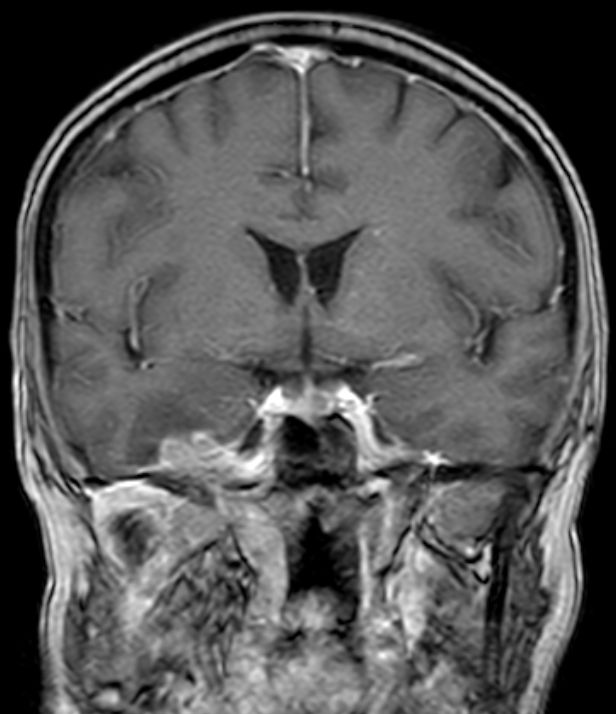

| Schädelbasis | 62-jährige Frau, bei der vor 2 Monaten ein Plattenepithelkarzinom der Zervix FIGO IIIB mit Radiochemotherapie behandelt wurde. Die Uterusgröße hatte von 13 auf 6 cm abgenommen. Jetzt Aufnahme mit der Diagnose Apoplex. | |||

An der Basalfläche des rechten Temporallappens KM - aufnehmende RF.![]() |

![]() | |||

![]() |

Unklare Doppelkontur der Meningen des Halsmarks.![]() |

Ödem des rechten Temporallappens.![]() | |||